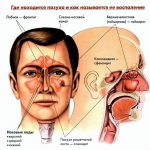

Гайморит у взрослых проявляется появлением нарастающей боли в районе носа. По утрам болезненные ощущения беспокоят меньше, но к вечеру нарастают. Голос становится гнусавый, носовое дыхание затруднено. Симптомы гайморита (фото 1) сопровождаются появлением выделений из носа, нарушением сна, повышенной утомляемостью, приступами кашля, появлением озноба.

Выглядит гайморит (см. фото 2) у взрослых и детей не очень приятно. Признаки гайморита у взрослых выражены потерей обоняния, появлением слезотечения, повышенным потоотделением. Так же появляется отечность на лице, неприятные запахи из носа, рта. Может присутствовать после приема пищи очень неприятное послевкусие – это тоже признаки гайморита у взрослых.

Одонтогенный гайморит

Гайморит может развиться после воспаления гайморовой пазухи под воздействием патологического процесса полости рта. Возбудителями обычно выступают стрептококки, микс-инфекция, кишечная палочка. Одонтогенный гайморит (фото 2) легко отличить по носовым выделениям.

Этот вид гайморита часто является односторонним. Заболевший человек спит беспокойно, часто появляется светобоязнь. Подробнее про другие виды читайте в статье что такое гайморит на нашем сайте.